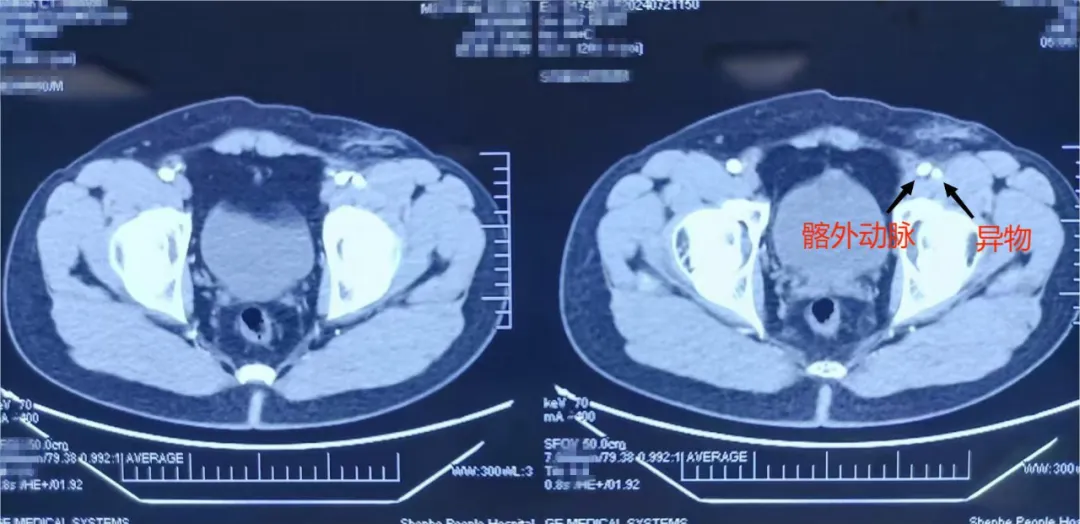

▲手术取出的铁片

▲专家团队手术中

接到患者后,急诊医学科团队迅速进行初步评估,完善相关术前检查及准备,随后创伤骨科和手足显微外科立即将患者收入,立即准备进行手术治疗。此时麻醉科手术室已经做好了手术室的准备,创伤骨科和手足显微外科主任刘丹、主治医师殷楚明及医师王彩石紧急为患者施行手术治疗,在麻醉科手术室团队及手术护理团队的积极配合下,术中使用C臂X光机定位,探查见铁片存在于股神经外膜及髂外动脉之间,刘丹主任在充分保护神经、血管下,仅用了1个小时就成功取出了患者体内的”定时炸弹”,术中未损伤腹股沟区血管、神经,术后患者生命体征平稳,转入创伤骨科和手足显微外科病房进一步救治。